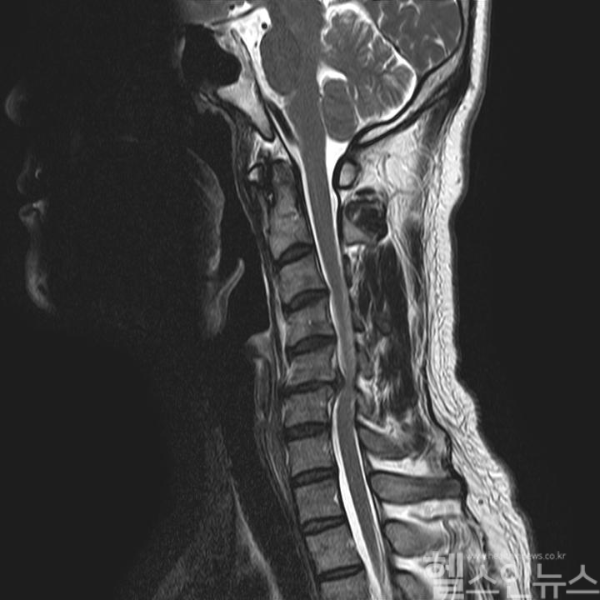

목디스크란 경추 사이에서 충격을 흡수하는 조직인 추간판이 탈출하거나 파열하면서 신경을 누르며 통증을 유발하는 질환이다. 스펀지처럼 말랑말랑한 디스크가 돌출되면 목이나 팔로 가는 신경을 압박하게 되는데 이로 인해 염증, 저림 증상 등이 발생하게 된다.

양방향 척추내시경을 이용한 목디스크 수술은 목 뒤에 1cm 이하의 미세한 구멍 두 개를 통해 한 쪽에는 내시경을, 다른 한쪽에는 수술 도구를 넣어 진행하는 수술법이다. 초고화질의 내시경으로 시야를 확보하고 병변을 눈으로 직접 확인하면서 치료하기 때문에 수술의 정확도가 높다. 또한 절개 부위가 작기 때문에 출혈이 적고 조직, 근육 손상이 적기 때문에 회복도 빠르고 상대적으로 안전한 수술이라고 볼 수 있다. 때문에 고령의 환자도 안전하게 받을 수 있는 수술이다.